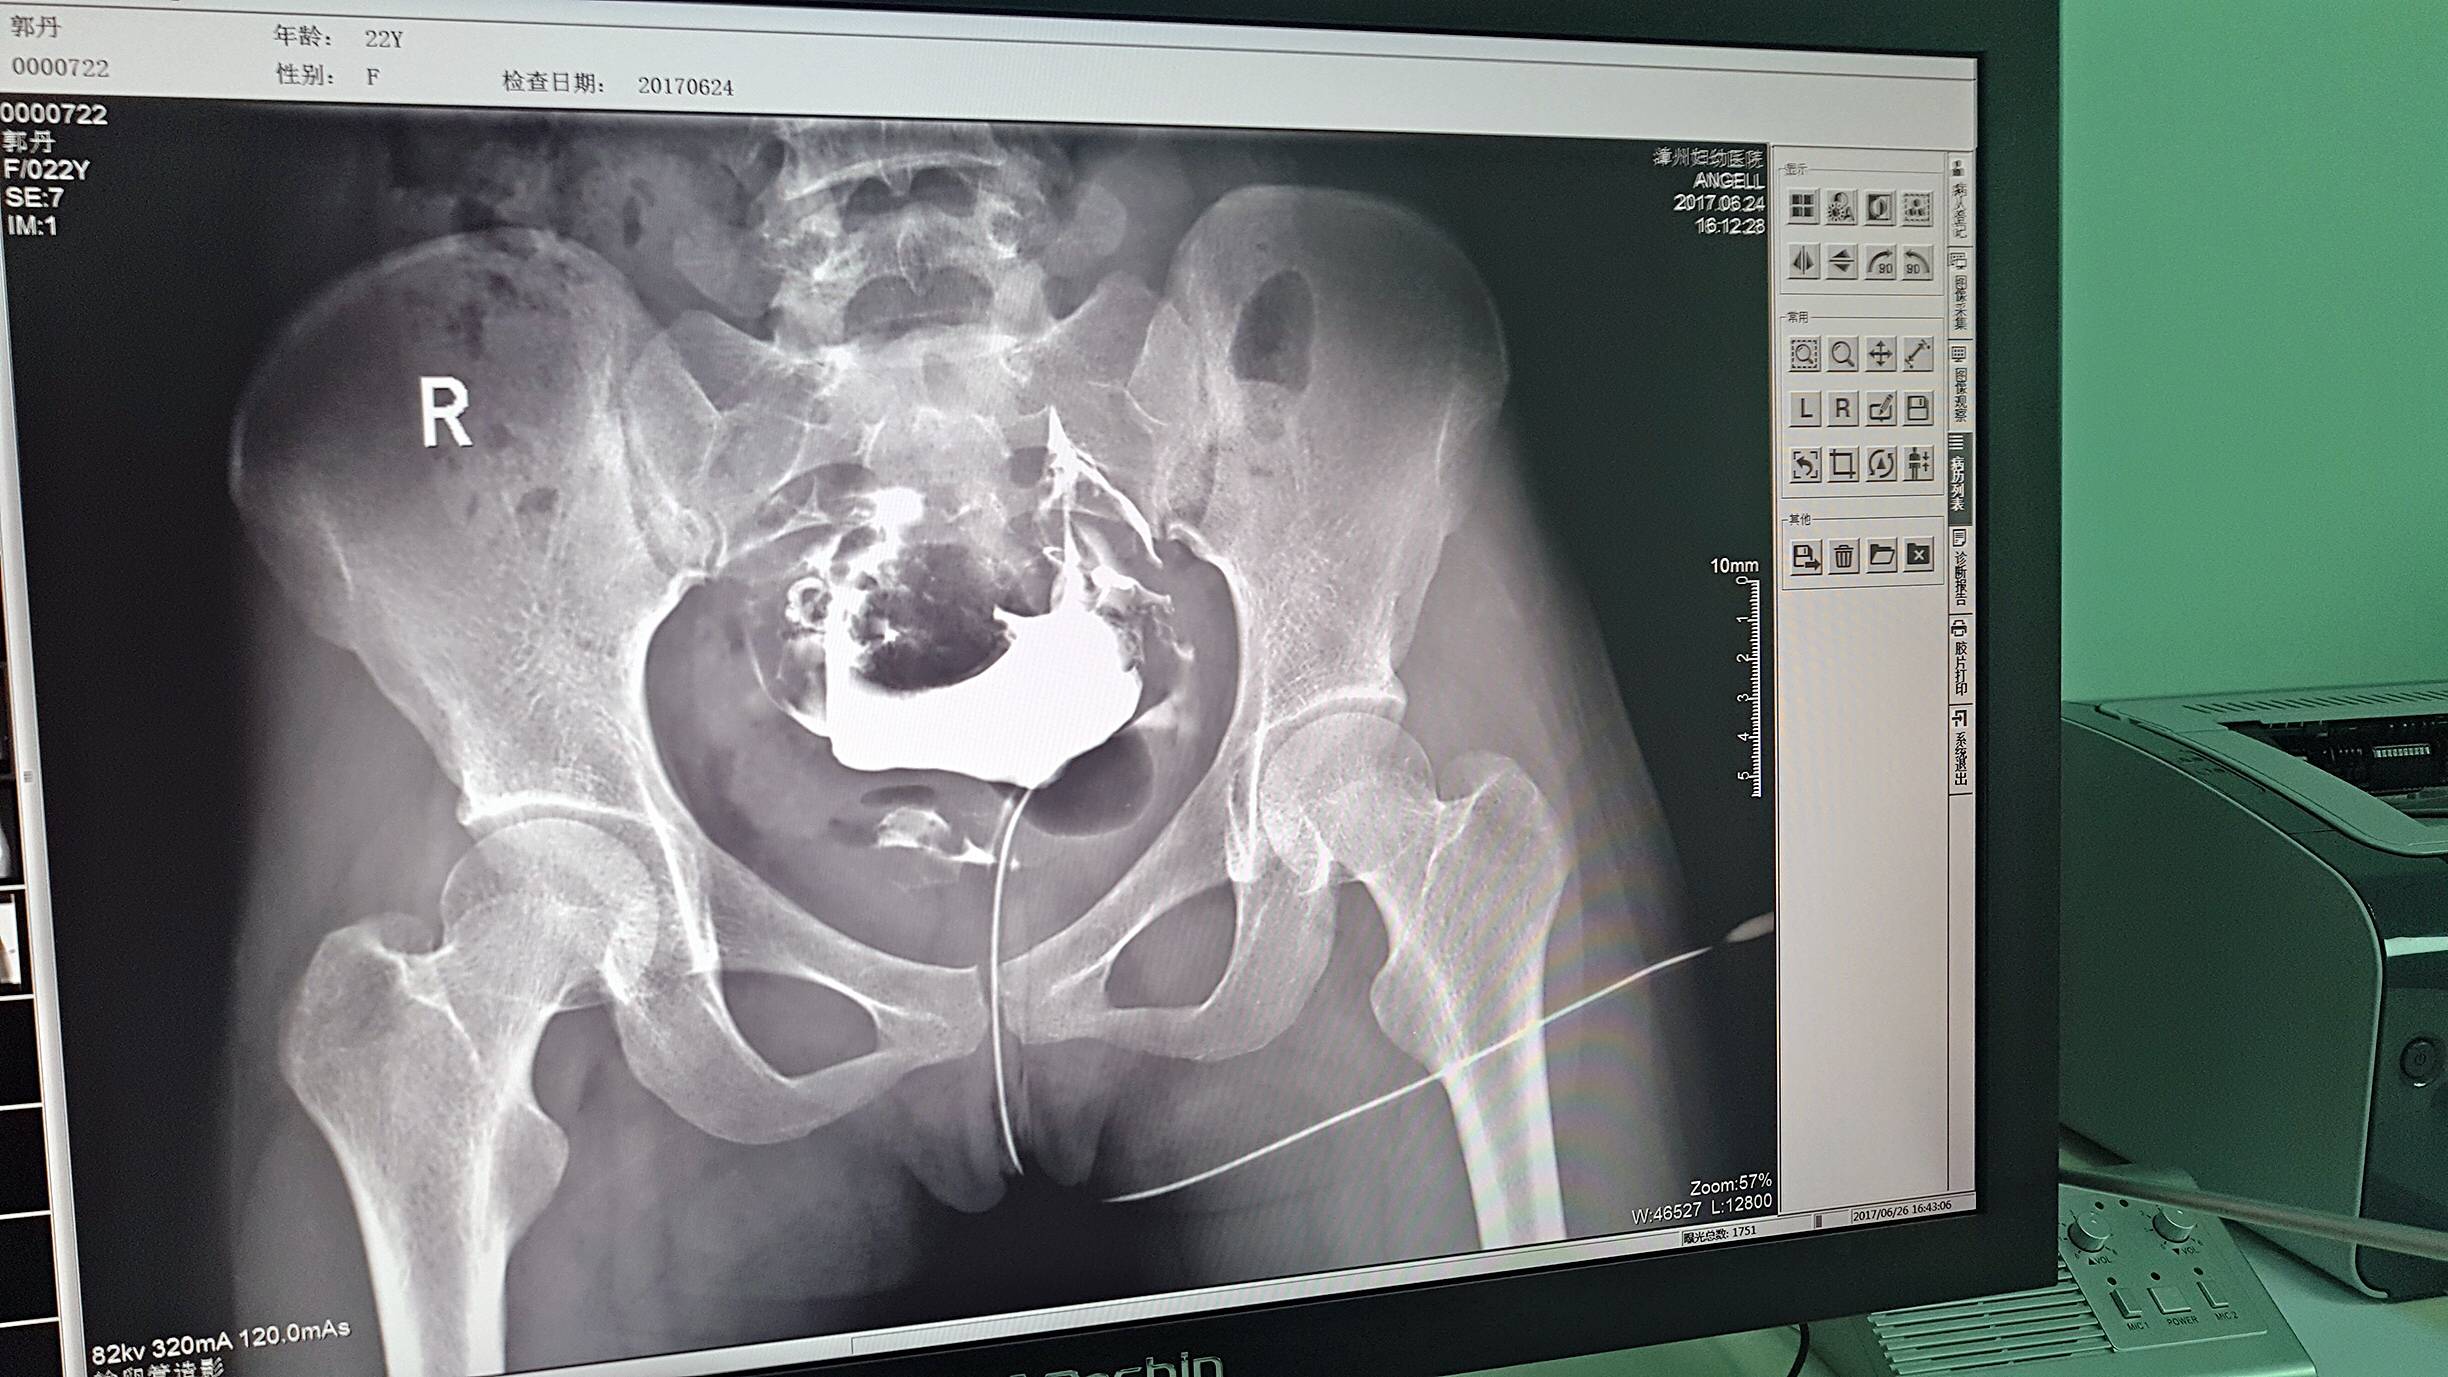

目前设备除了用于常规拍片之外,主要用于输卵管造影检查,平均每个月有超过20个患者在漳州妇幼医院做输卵管造影检查。在此之前,漳州市只有市医院、175解放军区医院等大三甲医院才能做输卵管造影检查,这不仅让三甲医院人满为患,而且下级医院却因为不能做某项检查而造成资源浪费。因为有了设备,漳州妇幼医院可以满足患者的一些特殊检查需求,已经有很多患者慕名而来。

漳州妇幼医院放射科的陈主任日常跟这台设备打交道是最多的,他最有发言权。在亿万28入口网页版-亿万28网页在线玩-万28官网下载最新版-亿万e网址pg-亿万28pg电子-亿万28赏金女王-亿万28娱乐科技的回访中,陈主任说:这台设备具备先进的诊断功能,操作方便,能够拍摄出清晰的影片,进而对患者病情能够实现精准诊断。同时在医院对患者诊断能力方面有较大提升,留住了大量患者,为患者提供了更好的医疗服务。